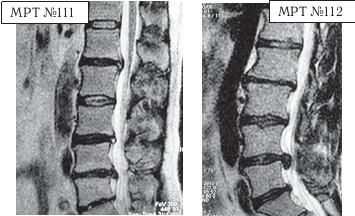

МРТ № 3

На МРТ № 3 — поясничный отдел позвоночника. (На данном «контрольном» снимке наблюдаются остаточные явления дегенеративно-дистрофического процесса в сегменте LV-SI после устранения методом вертеброревитологии секвестрированной грыжи межпозвонкового диска.)

В поясничном отделе форма позвоночного канала, создаваемая телом и дужками позвонка, вариабельна, но чаще она пятиугольная. В норме позвоночный канал в пояснично-крестцовом отделе сужен в переднезаднем диаметре на уровне LIII и LIV позвонков. Его диаметр каудально увеличивается, и поперечное сечение канала приобретает форму, близкую к треугольной, на уровне LV-SI. У женщин канал имеет тенденцию к расширению в нижней части крестцовой области. Сагиттальный диаметр значительно уменьшается от LI к LIII почти неизменен от LIII к LIV и увеличивается от LIV к LV. В норме переднезадний диаметр позвоночного канала в среднем равен 21 мм (15–25 мм).

Существует простая и удобная формула определения ширины позвоночного канала:

нормальный сагиттальный размер не менее 15 мм;

11–15 мм — относительный стеноз;

менее 10 мм — абсолютный стеноз. Уменьшение этого соотношения свидетельствует о сужении канала.

Высота поясничных межпозвонковых дисков 8–12 мм, нарастает от LI до LIV-LV, обычно уменьшается на уровне LV-SI